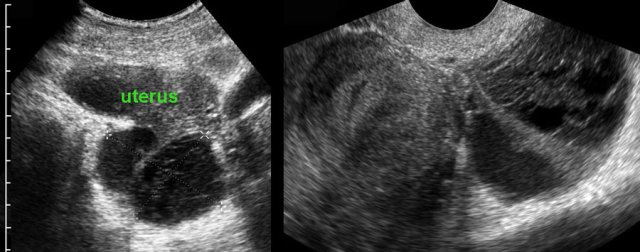

TOA case 4 (infected endometriotic cysts)

These images are of a 29-year old woman, suspected for appendicitis. CRP 185, WBC 17.

US shows a normal compressible appendix, thereby excluding appendicitis.

Large, thick-walled, septated cystic structures, filled with debris-like material, were found on both sides of the uterus (ut.), touching each other posteriorly (“kissing ovaries”).

This is somewhat suspect for bilateral infected endometrotic cysts.

The patient was treated with antibiotics and laparoscopic drainage.

There was a protracted course, but eventually regression of the abnormalities.

An MRI six months later, demonstrated all the signs of deep infiltrating endometriosis, also invading the rectum, thereby confirming the diagnosis of endometriosis.